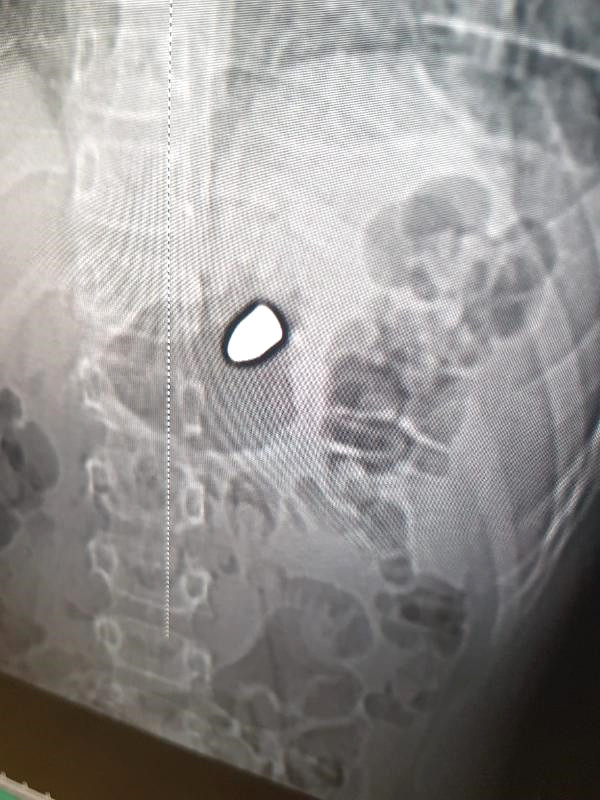

Şanlıurfa'da anne ve babasıyla birlikte bir sosyal tesiste oturan 8 yaşındaki Arda Şeyhanlıgil, kim tarafından ateşlendiği henüz belirlenemeyen tabancadan çıkan kurşunun göğsüne isabet etmesiyle yaralandı. Yaralanan Arda'ya ilk müdahaleyi, doktor olan babası gerçekleştirdi.

Olay, cumartesi günü Karşıyaka Mahallesi'nde bulunan GAP Sukay Sosyal Tesislerinde meydana geldi. Ailesiyle birlikte sosyal tesiste oturan Arda Şeyhanlıgil, kim tarafından ateşlendiği bilinmeyen tabancadan çıkan kurşunun göğsüne isabet etmesiyle yaralandı. Kanlar içerisinde yere yığılan ve ilk müdahalesi doktor olan babası Hikmet Şeyhanlıgil tarafından yapılan Arda, Harran Üniversitesi Tıp Fakültesi Hastanesi'ne götürdü. Yoğun bakım ünitesinde tedavisi süren Arda'nın gözü yaşlı yakınları, magandanın bir an önce bulunmasını istedi.